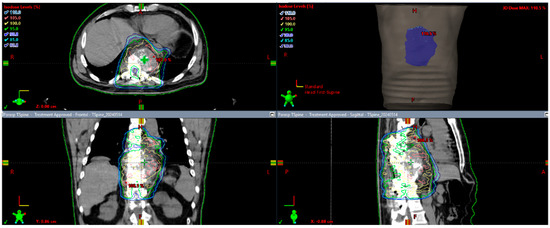

A 65-year-old male with a history of hypertension and vitreous degeneration presented with a four-year history of back pain refractory to physical therapy and medical management. An MRI showed a large hyperenhancing lesion on T1- and T2-weighted sequences involving the left side of the T9–T11 vertebrae with severe central canal and neuroforaminal stenosis at T9–T10 and T10–T11. Additionally, there was marrow replacement in the left lateral aspect of the T4 body. The T5 and T6 vertebral bodies may have also had infiltration, consistent with multilevel vertebral involvement (Figure 1).

Figure 1. MRI demonstrates a lesion with multivertebral involvement with severe invasion of T10.